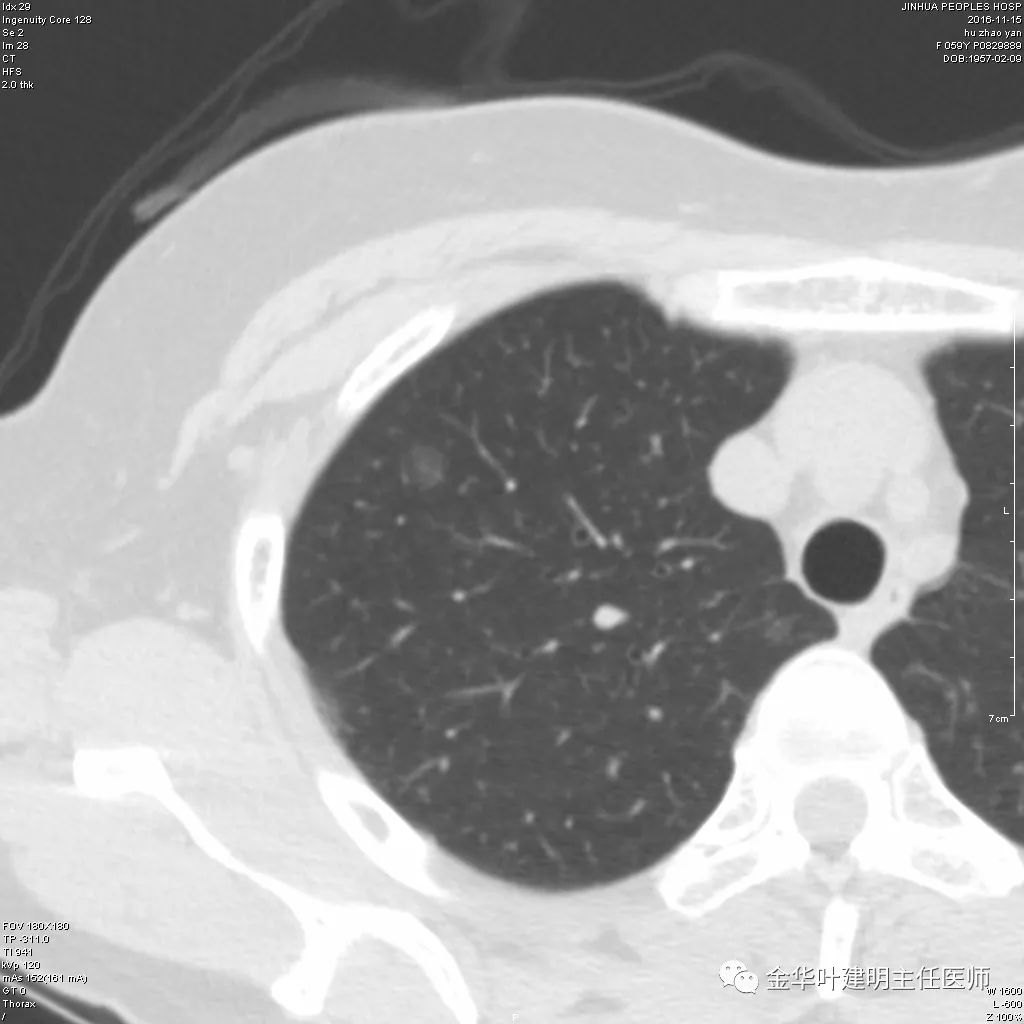

【经典课堂】肺原位腺癌

1080x810 - 98KB - JPEG

1080x810 - 64KB - JPEG